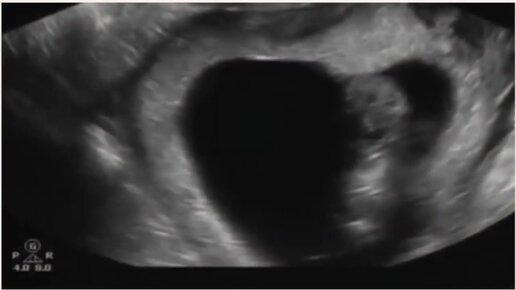

УЗИ на 11 неделе беременности